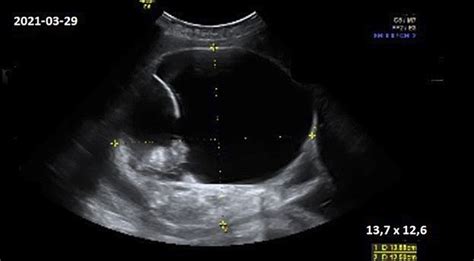

Daugiavaisio nėštumo atveju ultragarsiniai tyrimai pirmuoju nėštumo trimestru turi savų ypatumų. Svarbu įvertinti kiekvieno vaisiaus vystymąsi atskirai, stebėti placentų ir vaisiaus vandenų kiekį, atsižvelgiant į tai, kad dvynių ar daugiau vaisių nėštumas yra laikomas didesnės rizikos nėštumu. Tolimesnė priežiūros taktika tokiu atveju yra itin individualizuota ir glaudžiai susijusi su ultragarsiniais tyrimais bei kitais medikų sprendimais.